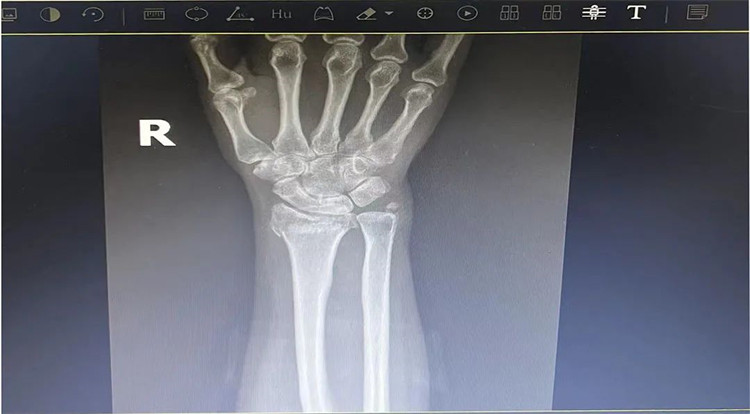

患者老年女性,50多歲,在騎電動車停下時因電動車倒下,右手著地,當(dāng)即感覺,右腕及骶尾部腫痛伴右關(guān)節(jié)畸形、活動受限,急來我院就診。門診醫(yī)師結(jié)合病史、查體及輔助檢查后,診斷為:右橈尺骨遠端骨折、骶尾部挫傷并收入住院部。